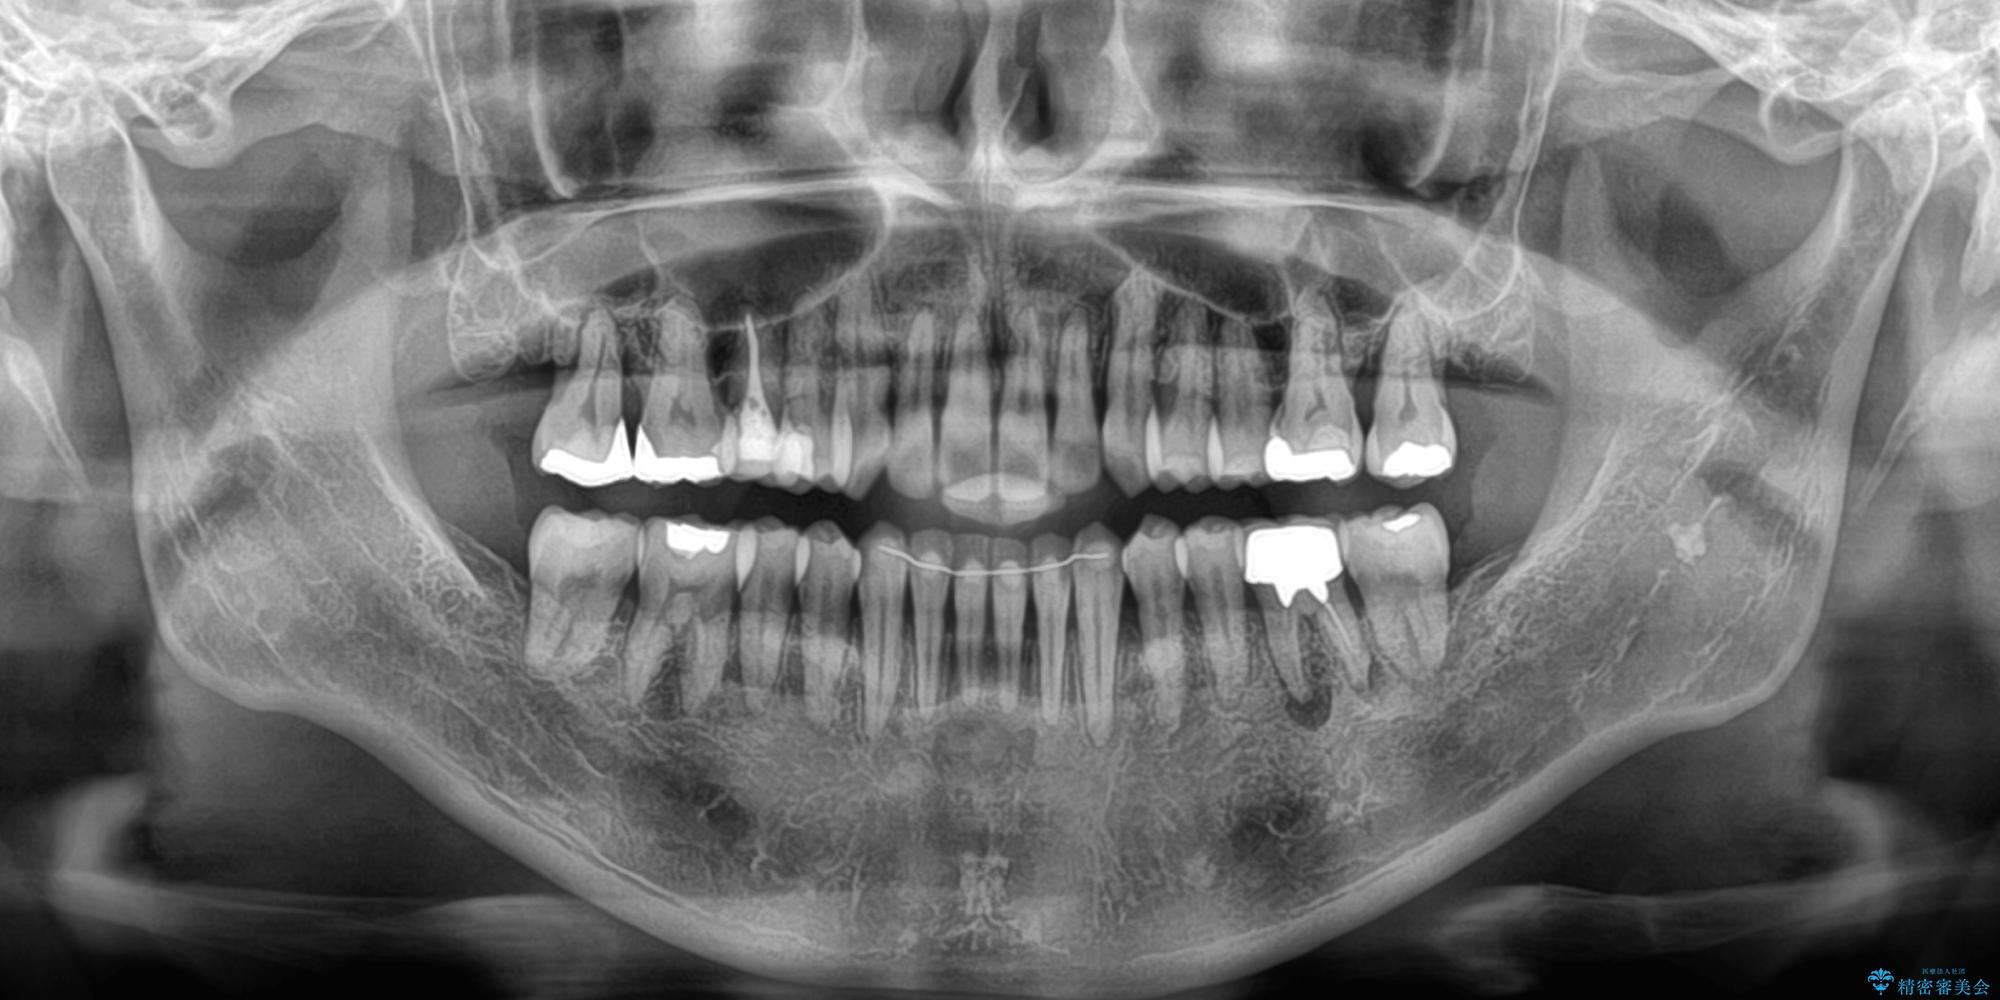

- 前歯のデコボコや八重歯を治したいとのことで来院された患者様です。

受け口傾向の骨格であり、前歯はクロスバイトまたは切端咬合となっており、下顎を中心に歯列全体の後方移動を行い、IPR(歯と歯の間を削る)によってデコボコが解消するように設計し、インビザラインにより治療を行うこととしました。

受け口傾向のインビザライン矯正は比較的治療を行いやすいため、きれいに仕上げることができました。舌の突出癖が顕著であったため、改善のためのトレーニングをしっかりと行っていただきました。